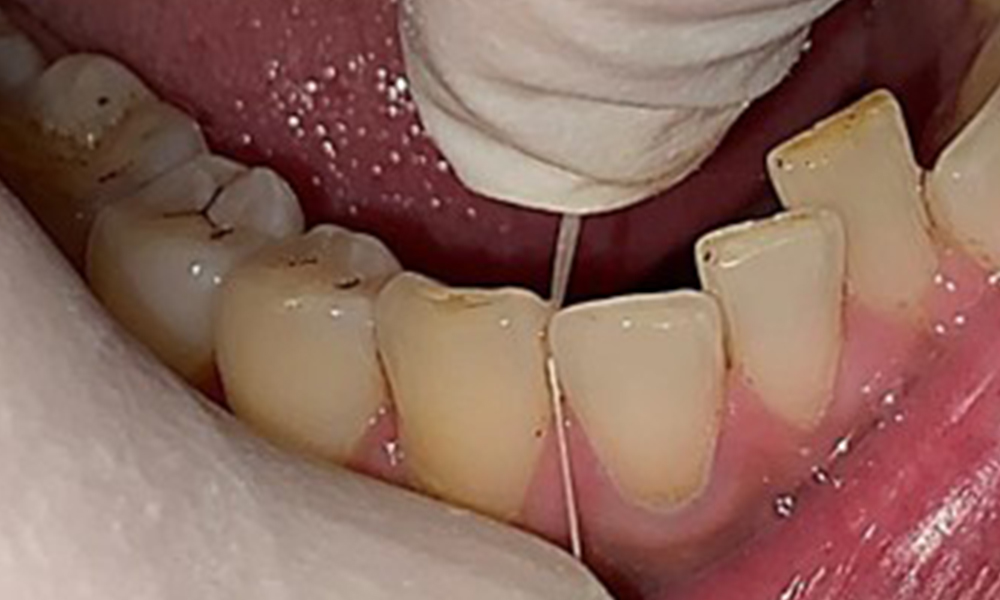

Instruktion & Motivation sind wichtige Bestandteile in der Sitzung. Gutes

häusliches Mundhygieneverhalten und – verständnis sind dem Patienten wichtig. Es zeigen sich insbesondere an den ZahnhalsbereichenPlaqueakkumulationen (Abb. 8).

Diese sind mit dem Patienten zu besprechen und Verbesserungen in der Zahnputztechnik zu üben. Gerade aufgrund der Erosionen und Attritionen ist ein weicher Zahnbürstenaufsatz für die häusliche Mundhygiene anzuraten.